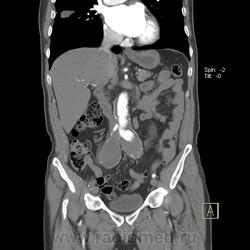

Пациент лежит в кардиологии. Прислали на аортографию. 2 врача УЗИ несколько разошлись в диагнозах: одна видит тромбированную аневризму брюшной аорты, другая - тромбоз нижней полой вены.

А мы получили вот такие красивые картинки.

Шикарно! Тромбированная аневризма инфраренального отдела (над бифуркацией), бифуркации и общих подвздошных артерий, синдром Лериша справа.

И еще маленькая аневризмочка наружной подвздошной слева. Честно говоря, меня больше всего впечатлили коллатерали, благодаря которым клинически он вообще не соответствует исследованию. Конечности теплые, пульсация слабая, но как-то прослеживается...